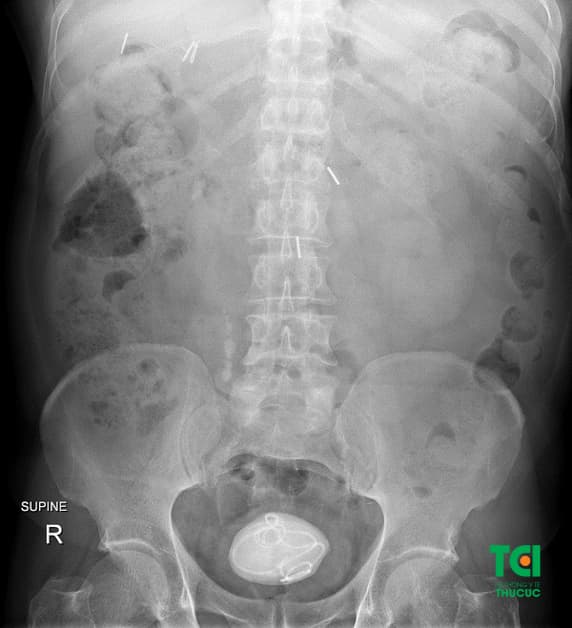

Bệnh nhân đến Thu Cúc TCI điều trị sỏi bàng quang kích thước lớn, gây nhiều triệu chứng bệnh